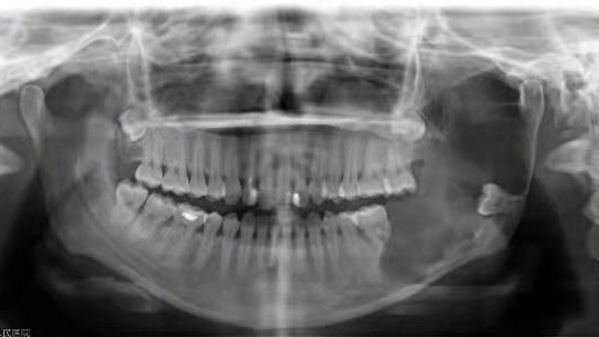

患者小張(化名)是一位年輕女性,因左側下頜骨漸大2月余到我院口腔科就診,檢查后被確診為下頜骨成釉細胞瘤,該腫瘤多發生在下頜骨,以下頜體、下頜角多見,腫瘤進一步發展可侵犯周圍軟組織。

據口腔科副主任醫師劉彥杰介紹,由于患者腫瘤侵襲的范圍較大,徹底治療只能截斷下頜骨切除腫瘤。但這就意味著,術后將會出現明顯的面部塌陷,即便用軟組織修復,也會影響面部和口腔功能進食、說話都受影響……